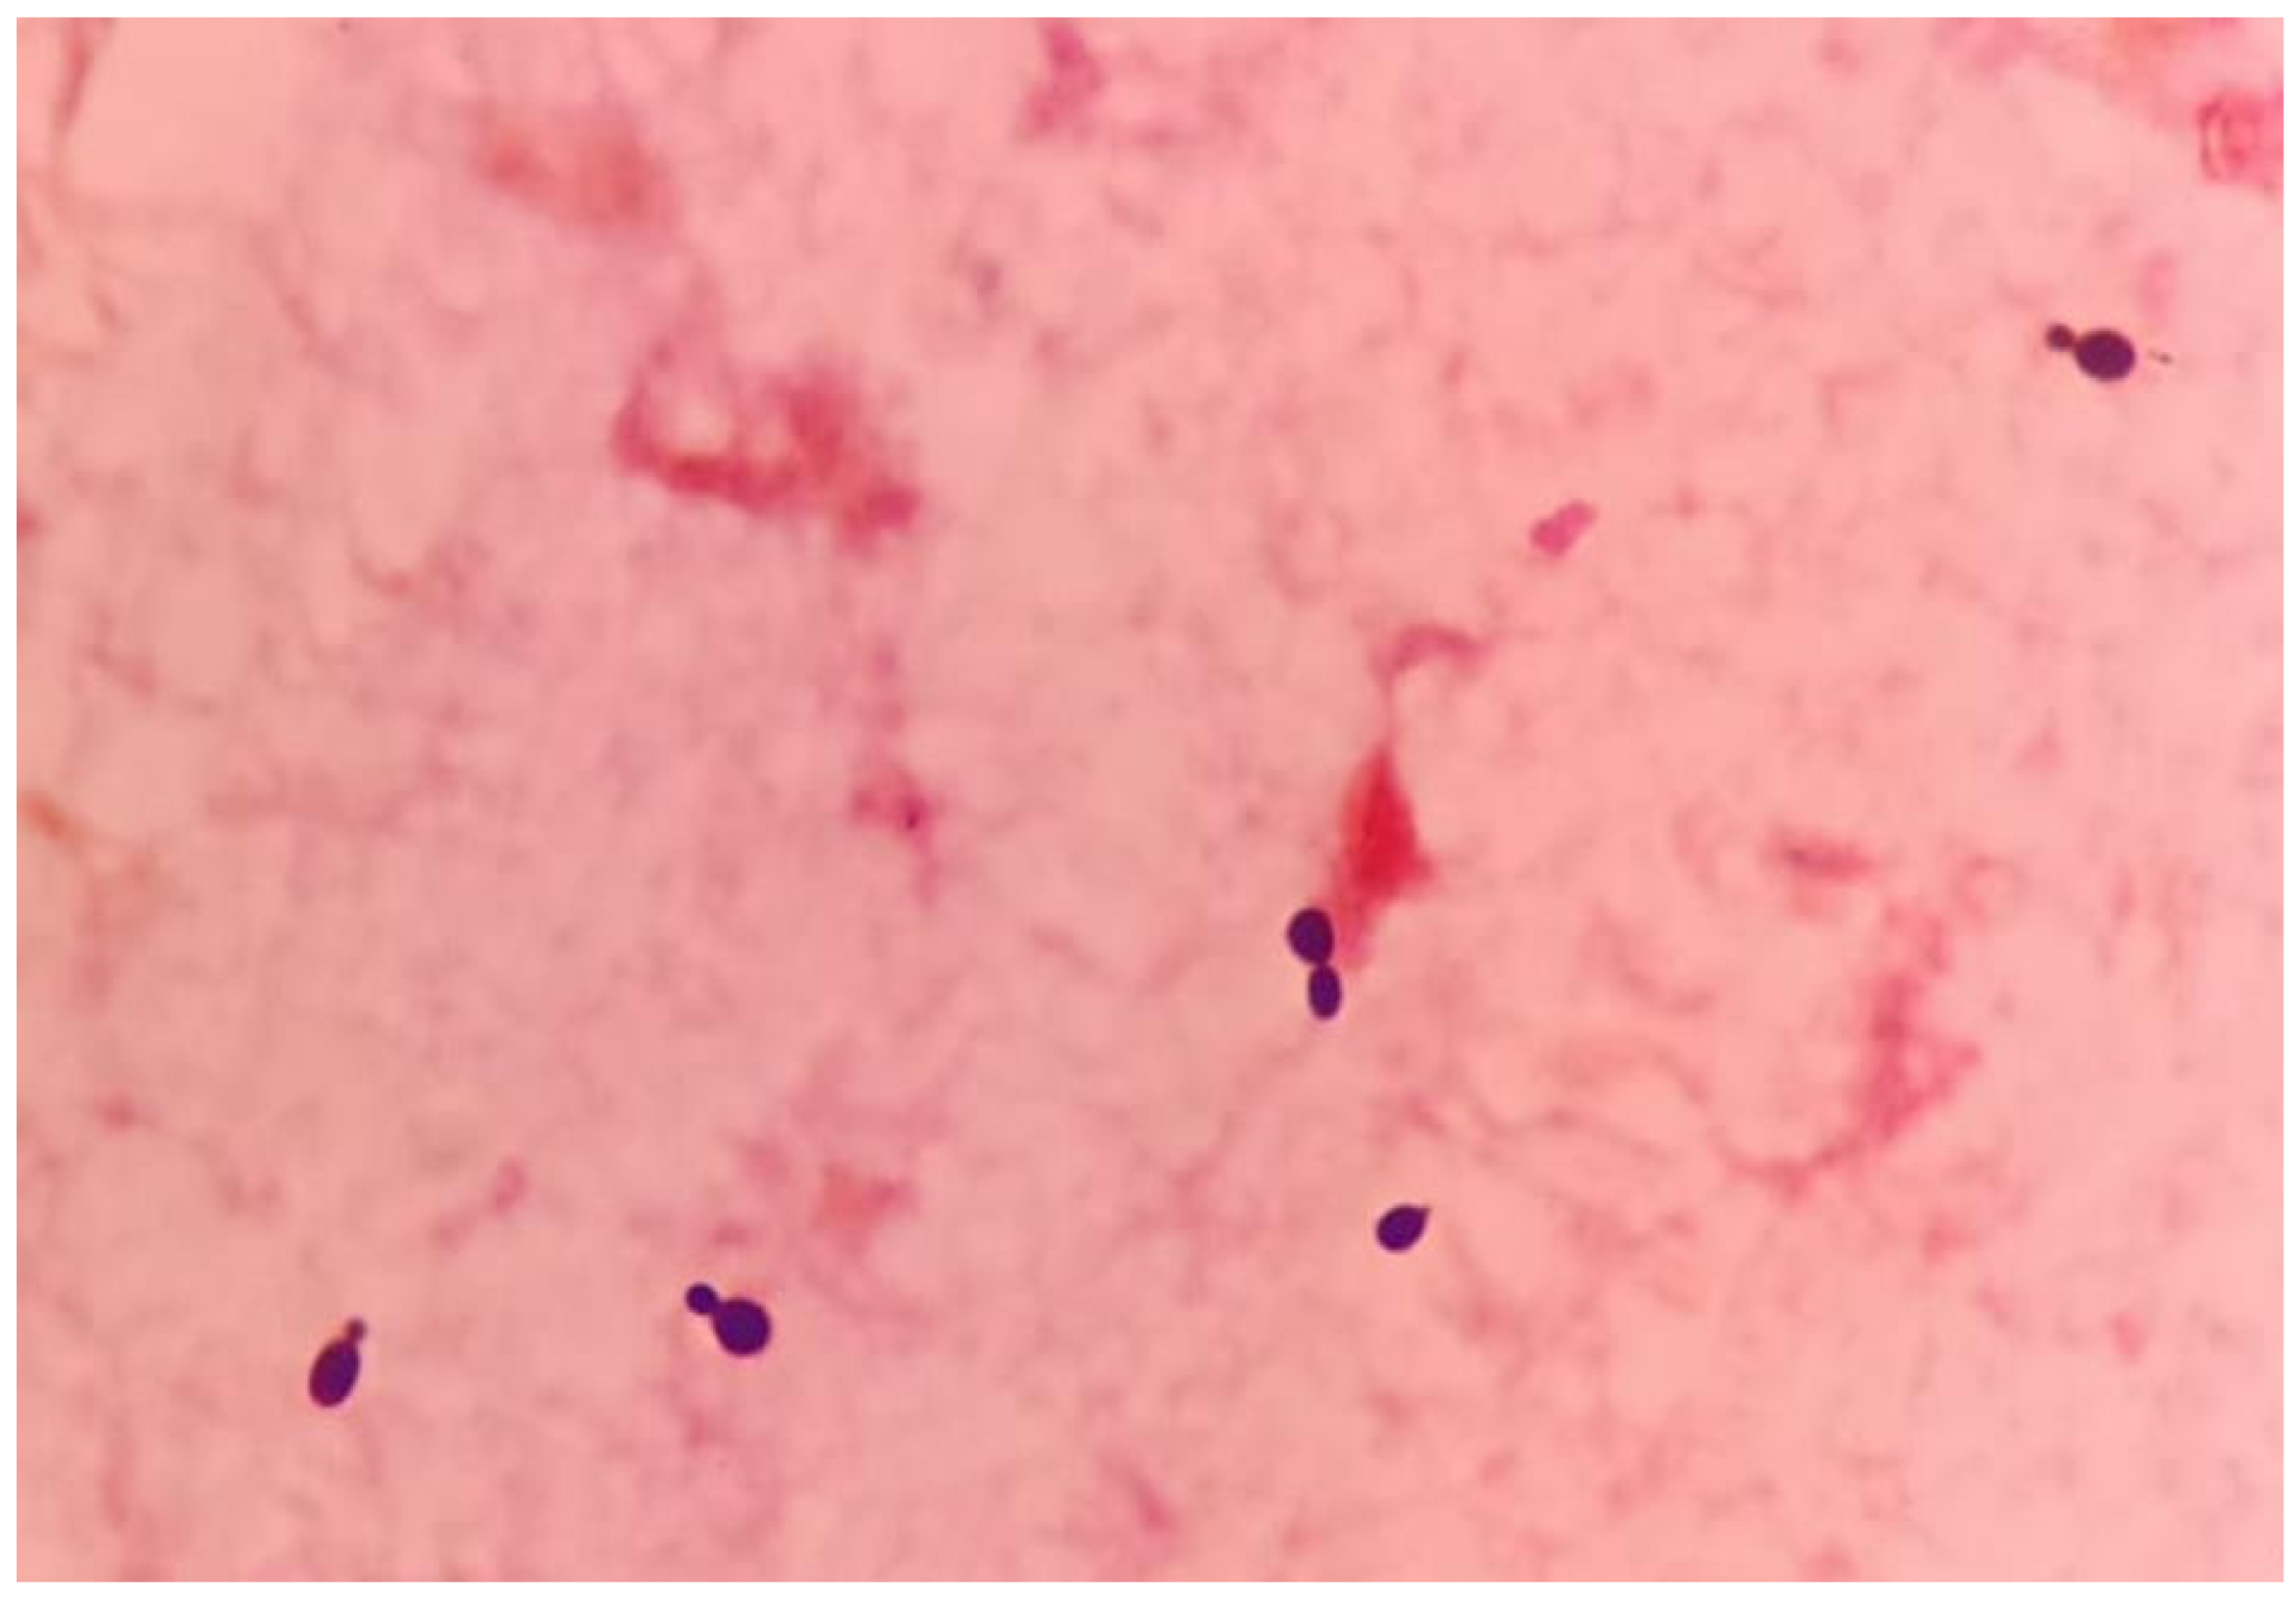

Following urgent adequate source control via hemi-hepatectomy and biloma removal along with empirical antimicrobial coverage, the patient remained hemodynamically unstable, requiring vasopressors. Septic parameters including procalcitonin were persistently elevated, pointing towards unresolved infection states. Repeated blood culture and sensitivity testing for both bacterial and fungal specimens, which were sent pre-operatively, further identified and reported as salmon-pink colonies, and an early clue of the presence of yeast and subculture onto mycological isolation media revealed that the growth was Rhodotorula mucilaginosa (Figure 2 and Figure 3).

Figure 3. A Gram stain of the positive blood culture showing budding yeast cells (1000× magnification). The yeast was identified as Rhodotorula mucilaginosa (%ID: 91.9) through biochemical means using the ID 32 C kit (Biomerieux, Marcy-l’Étoile, France). Our isolate’s identity was further confirmed by matrix-assisted laser desorption ionization–time of flight mass spectrometry (MALDI Biotyper, Bruker-Daltonics, Bremen, Germany), which matched its mass spectral pattern with that of Rhodotorula mucilaginosa DSM 70403 DSM.